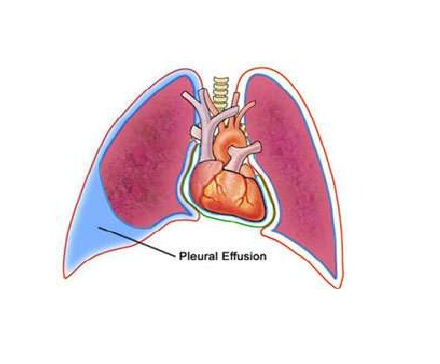

Симптомы и причины скопления воды в легких

Раздел: Ракурсы просвещения